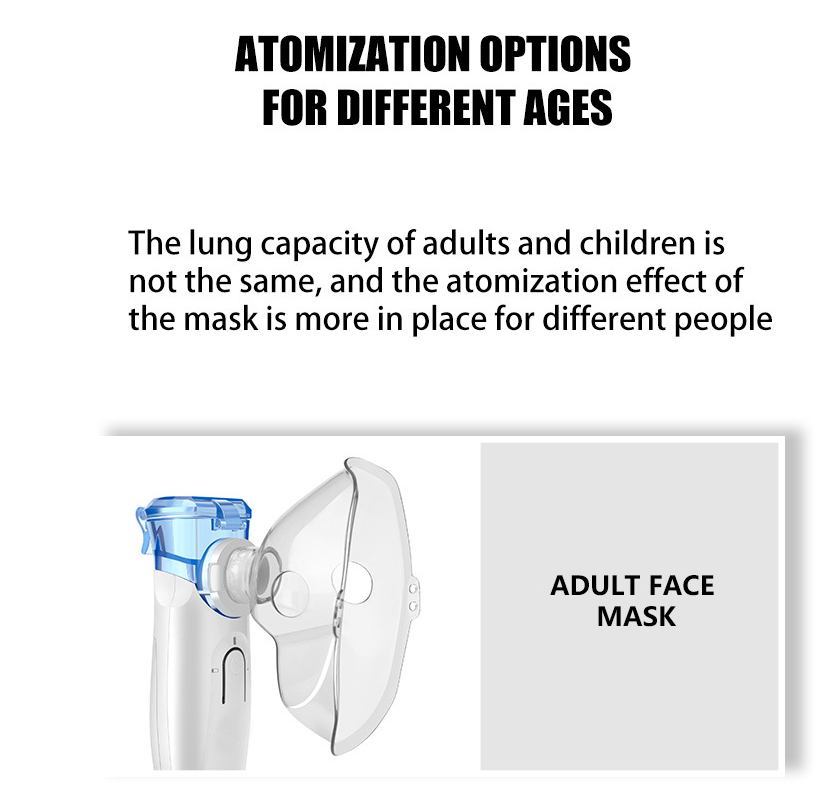

Experience the convenience of the Portable Micro Net Atomizer, your go-to solution for on-the-go inhalation therapy. This handheld nebulizer is designed for both ease of use and effective medication delivery, making it perfect for those who need respiratory relief anytime, anywhere.

Featuring a sleek design and lightweight construction, this atomizer is powered by either dry or lithium batteries, ensuring you have the flexibility to use it whenever you need. Its compact size makes it easy to carry in your bag or pocket, allowing you to maintain your health regime without interruption.

With its advanced micro-net technology, the nebulizer delivers medication in fine mist form, ensuring maximum absorption and effectiveness. Whether you are dealing with allergies, asthma, or other respiratory issues, this device will provide you with the relief you need.

Introducing the Outdoor Portable Nebulizer, your essential companion for quick and effective asthma relief! Designed for both kids and adults, this silent mesh mini inhaler is perfect for on-the-go use, ensuring that you can manage breathing difficulties anytime, anywhere.

This sleek and compact nebulizer comes equipped with everything you need for a seamless experience:

Whether you're at home, work, or outdoors, the Outdoor Portable Nebulizer ensures you have access to essential respiratory care. Its compact design and lightweight build make it easy to carry in your bag.